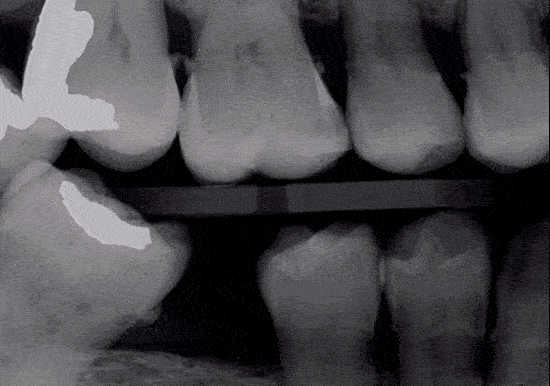

With the state-of-the-art digital X-ray technology, our patients can receive the necessary care without unnecessary radiation. Diagnostic X-rays play an invaluable role in the diagnosis of dental problems. With the digital format, we are able to evaluate and diagnose many conditions, often before they become problematic.

In addition, this is accomplished with up to 1/10 the radiation exposure of the traditional film format. Also, the images are instantly loaded on our computer monitors and help the doctors effectively communicate information about your oral health.

X-ray Scan using Overjet Ai Integration

In addition to our doctors evaluating every x-ray taken for our patient’s. At Barranca Canyon Dentistry, we also incorporate AI scanning of all of the x-rays. This allows an overlay with clear visuals to help our patient’s understand what is visible on each image. The AI software will show items such as cavities, existing fillings, infections, gum disease and so much more.